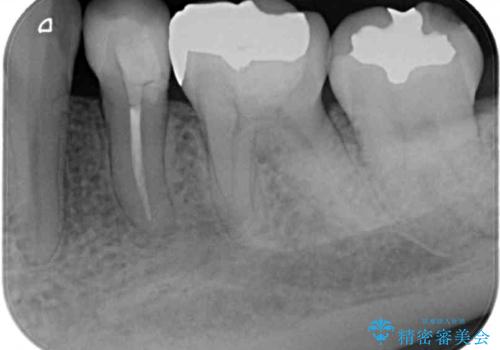

矯正の後戻りの改善と銀歯をセラミックに

- 上下前歯の叢生を気にして来院された患者様です。

矯正治療後には、下顎臼歯の目立つ銀歯をセラミックインレーにて修復治療を行いました。

口を開けたときに金属が見えなくなり、患者様には大変満足していただきました。